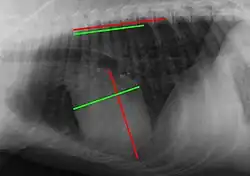

Der VHS wird zumeist anhand einer Röntgenaufnahme des Brustkorbs in Seitenlage bestimmt. Auf dem Röntgenbild werden die Strecke von der Aufzweigung der Luftröhre zur Herzspitze sowie eine rechtwinklig dazu verlaufende Strecke an der breitesten Stelle des Herzens ermittelt.[1][2] Für Hunde mit einer starken Vergrößerung des linken Vorhofs schlägt Buchanan vor, das obere Ende der Längsachse am angehobenen linken Bronchus anzusetzen. Bei älteren Katzen, bei denen die lange Herzachse oft fast parallel zum Brustbein verläuft, wird statt der Luftröhrenaufzweigung die Basis der Vene des vorderen Lungenlappens als Messpunkt empfohlen. Die Vermessung der Herzachsen kann auch auf einer Röntgenaufnahme in Rückenlage erfolgen.[3] Allerdings ist beim Hund bei dieser Projektion der linke Vorhof nicht an der Bildung der Herzsilhouette beteiligt.[4]

Die beiden Strecken werden auf die Brustwirbelsäule, beginnend jeweils am Vorderende des vierten Brustwirbelkörpers, übertragen. Anschließend wird die Anzahl der Wirbel bestimmt, die diese Strecken einnehmen. Wenn das Ende der Strecke keinen ganzen Wirbel mehr umfasst, wird dieser Teilwirbel auf ein Zehntel genau ermittelt: Reicht also beispielsweise die Länge der Längsachse vom Anfang des vierten bis zur Mitte des neunten Brustwirbels, so beträgt der Wert für diese Strecke 5,5.[1][2] Die Länge eines Wirbelkörpers zusammen mit der zugehörigen Bandscheibe dient dabei als ein die Größe des Individuums reflektierendes, relatives Längenmaß. Da die Wirbelkörperlängen innerhalb der Wirbelsäule variieren, ist es von Bedeutung, stets mit einem definierten Wirbel zu beginnen. Der in der Humanmedizin zur Größenbeurteilung des Herzens herangezogene Herz-Thorax-Quotient ist bei Hunden wegen der großen Rasseunterschiede in der Brustkorbform nicht geeignet.

Der Vertebral Heart Score ist die Summe der Wirbel, die Längs- und Querachse einnehmen. Ein VHS bis 10,5 (Hund) bzw. 8,1 (Katze) gilt als normal, höhere Werte sprechen für eine Herzvergrößerung (Kardiomegalie).[5] Für das Erkennen einer Herzverkleinerung (Mikrokardie) wird der VHS nicht herangezogen. Dafür wird die Anzahl der Zwischenrippenräume bestimmt, über die die Herzsilhouette reicht. Eine Herzverkleinerung ist in der Regel nicht durch eine Herzerkrankung, sondern durch einen Blutvolumenmangel bedingt. Das Herz nimmt dabei weniger als zwei Zwischenrippenräume ein.[6]